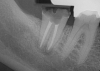

Fig 2. Final fill with the .04 taper 035 gutta-percha to the verified 29-mm working length.

Figure 2

Step 4. Use 035 File for Final Preparation

The canal was prepared with an 035 (.04 taper) NiTi rotary file to the 29-mm working length with large amounts of water-soluble gel (Figure 2). The rotary files were supplied in lengths of 21 mm, 25 mm, and 31 mm. The system provided matching paper points and gutta-percha in all file sizes. Irrigation took place with NaOCl before the solution was allowed to remain in the canals for 30 minutes. After the irrigation, CO2 laser technology was used for 20 seconds to eliminate bacterial and viral contaminants. The laser evaporated any residual bacteria or viruses that remained after irrigation. The laser was an effective modality for root-canal sterilization.4